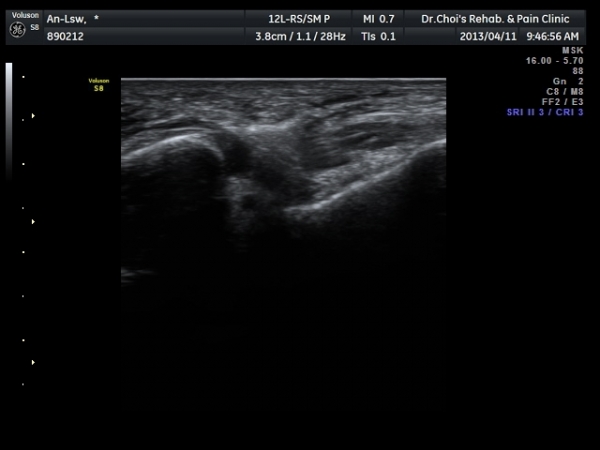

Àü°Å°ñºñ°ñÀδë Á¾´Ü¸é°Ë»ç»ó Àδë ÀδëÀÇ Àú¿¡ÄÚ ºÎÁ¾°ú(±×¸² 3)

ºñ°ñºÎÂøºÎ ¿¬°á¼º ¼Ò½ÇÀÌ °üÂûµÈ´Ù(±×¸² 4).

±×¸²3) Àü°Å°ñºñ°ñÀδë Á¾´Ü¸é°Ë»ç

±×¸²4) Àü°Å°ñºñ°ñÀδë Á¾´Ü¸é°Ë»ç